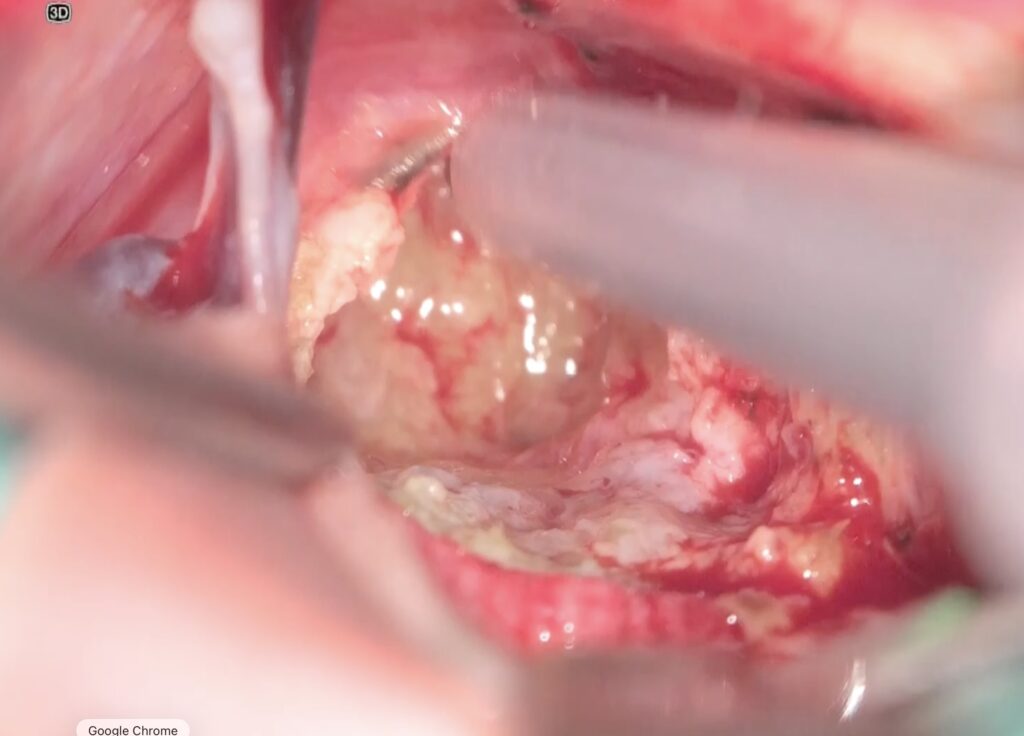

手術は通常通り行われ、顔面神経の麻痺を起こさずに摘出は終了し、うまくいったと考えていました。しかし術後より覚醒障害が続き、強い小脳腫脹を生じたため、術後脳室ドレナージ術、バルビタール麻酔療法、気管切開まで行い急性期を乗り切りました。術前より下肢静脈血栓症を合併していたことと、Petrosal veinが通常より広範囲の静脈環流を行っていたためと考えられます。現在、覚醒し、四肢が動くようになってきました。

手術は通常通り行われ、顔面神経の麻痺を起こさずに摘出は終了し、うまくいったと考えていました。しかし術後より覚醒障害が続き、強い小脳腫脹を生じたため、術後脳室ドレナージ術、バルビタール麻酔療法、気管切開まで行い急性期を乗り切りました。術前より下肢静脈血栓症を合併していたことと、Petrosal veinが通常より広範囲の静脈環流を行っていたためと考えられます。現在、覚醒し、四肢が動くようになってきました。